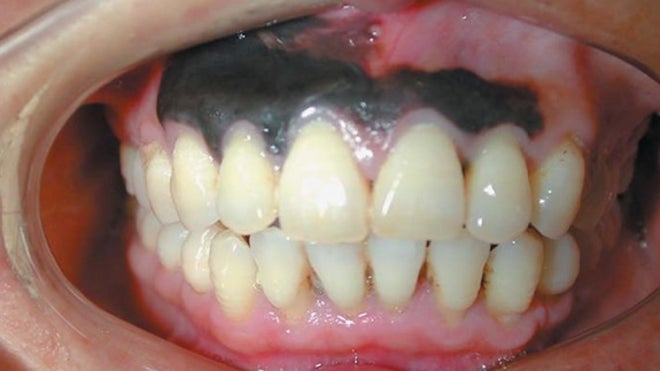

The area of the man's gums that was darkly pigmented measured about 0.5 inches wide by 1.5 inches long (1.5 centimeters by 4 cm). When a biopsy showed the dark lesion was, indeed, cancerous, doctors removed not only the gums but also parts of the man's upper jaw, according to the case report, published today (Oct. 9) in The New England Journal of Medicine. [Image of the mucosal melanoma]

Pigmentation in the mouth is not uncommon, and can be caused by many things, Muller noted. Although dark spots in the mouth might look like melanoma, they are usually benign. However, nothing other than melanoma would look like the black, large, diffuse pigmentation seen in this patient, Muller said.